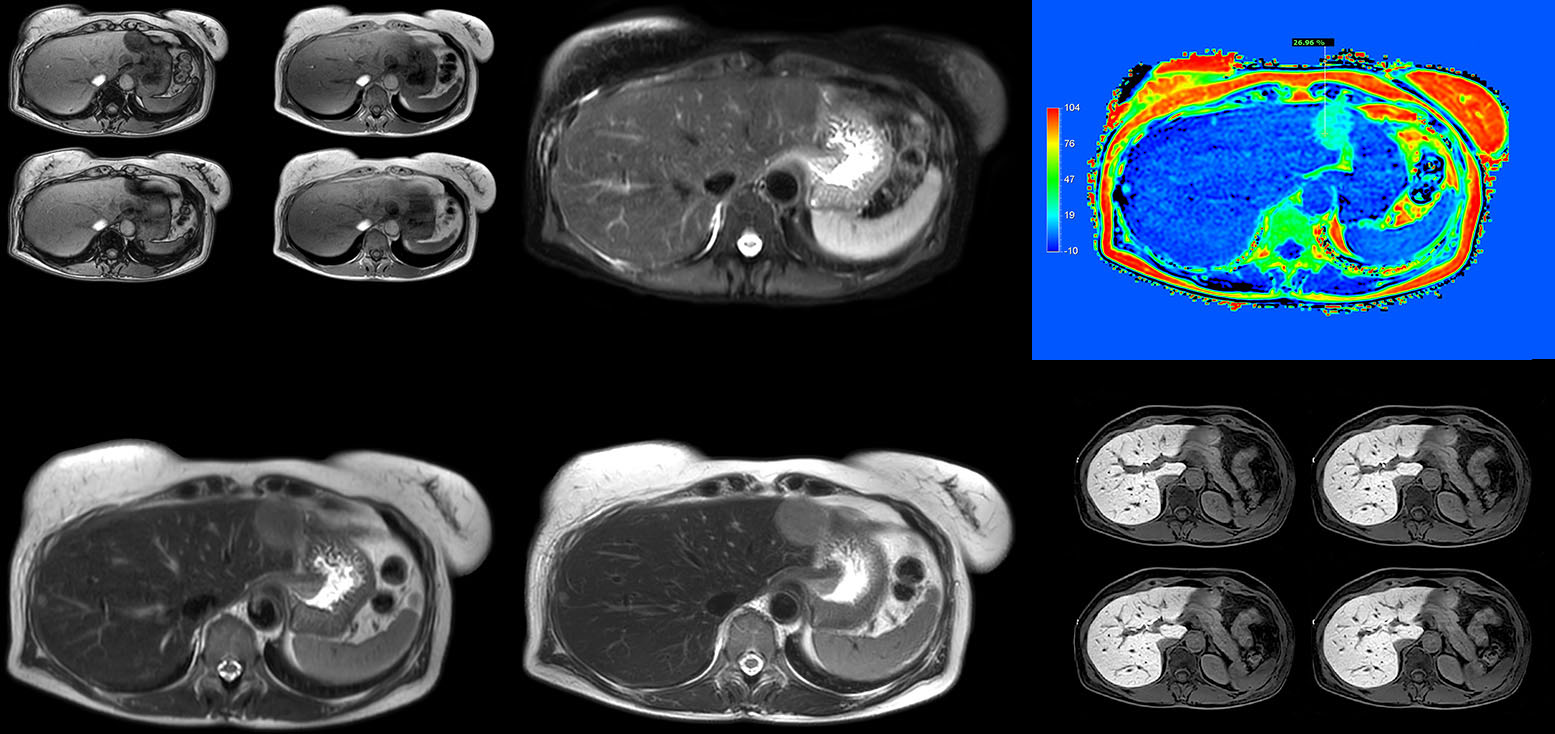

mDIXON Quant is a simple sequence to include in routine liver MRI

“We have performed a study comparing mDIXON Quant fat percentages with results from histopathology. The correlation with different histologic methods was very good and also the correlation with MR spectroscopy was far above 0.9 – a nearly perfect correlation,” says Dr. Kukuk.

“So, this fast mDIXON Quant sequence allows us to diagnose, quantify, and follow up – that’s the real advantage. Our gastroenterologists were easily convinced, as they are well aware of the limitations of ultrasound and the risks of liver biopsy.”

Non-invasive liver fat quantification in a breathhold with mDIXON Quant

“Fatty liver disease is a common condition. Studies found a prevalence of non-alcoholic fatty liver disease in up to 44% in the general European population [1]. Liver fat cannot be quantified by ultrasound or CT, so biopsy has been the way to quantify fatty liver disease so far,” says Dr. Kukuk. “mDIXON Quant now allows non-invasive quantification of liver fat, which is valuable for both diagnosis and follow-up during dietary changes or therapy, for instance in hepatitis C.”

“The mDIXON Quant fat fraction maps provide quantitative information and also anatomical detail. The sequence is fast, usually taking about 16 seconds, which is just a breath hold for most patients. It definitely improves our efficiency.”